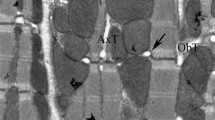

Human cardiomyopathy has been extensively studied in the last decade, and knowledge of the functional and structural alterations of the heart has grown. However, understanding of the pathogenesis has come mostly from experimental studies. A number of work have been designed to elucidate if alterations of the contractile apparatus of cardiac cells contribute to the impairment of heart mechanics in cardiomyopathies. As well, an important question is to be solved: whether energy supply of the contraction-relaxation cycle is sufficient in the myopathic heart. Use of cardiac fibers skinned by different techniques allows to evaluate functional ability of myofibrils, mitochondria and bound creatine kinase which plays an important role in cardiomyocyte energy metabolism. The data presented in this chapter show that experimental cardiomyopathies of various types have some common features. These are an increase in calcium sensitivity of myofibrils and a depression of functional activity of mitochondrial creatine kinase. Possible mechanisms and physiological significance of these changes are discussed.

Veksler VI, Kuznetsov AV, Sharov VG, Kapelko VI, Saks VA: Mitochondrial respiratory parameters in cardiac tissue: a novel method of assessment by using saponin-skinned fibers. Biochim Biophys Acta 892: 191–196, 1987